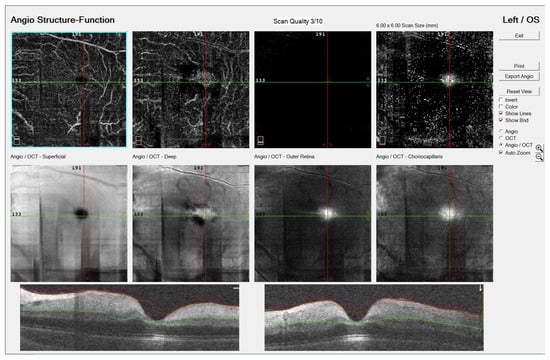

Six days prior to the ocular symptoms, chickenpox exanthema emerged. The patient was highly febrile for the first few days of the infection. There was no history of recent tick exposure. Visual acuity upon examination measured using the Snellen chart was 6/6 on the right eye (RE) and light perception on the LE. Pupil examination revealed a 1+ relative afferent pupillary defect of the LE. The anterior segment, intraocular pressure, ocular motility, orthoptic examination and ocular ultrasound were unremarkable. Dilated fundus examination displayed a normal fundus of the RE. The LE exhibited an appearance of CRAO: retinal whitening, a cherry-red spot, and arteriolar attenuation without distinguishable emboli (Figure 1).

Figure 1. Color fundus photography (FA, Zeiss FF 450 plus, VISUPAC software, Jena, Germany) of a six-year-old patient’s left eye with prominent features of central retinal artery occlusion: retinal whitening, a cherry-red spot, and arteriolar attenuation without distinguishable emboli.